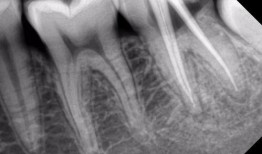

根管治疗视频,从视频学习根管治疗技巧与流程

最近牙疼得我简直要抓狂了!你知道那种感觉吗?就像有一颗小钢珠在你的牙髓里不停地滚动,痛得你连呼吸都小心翼翼。于是,我决定上网搜一...